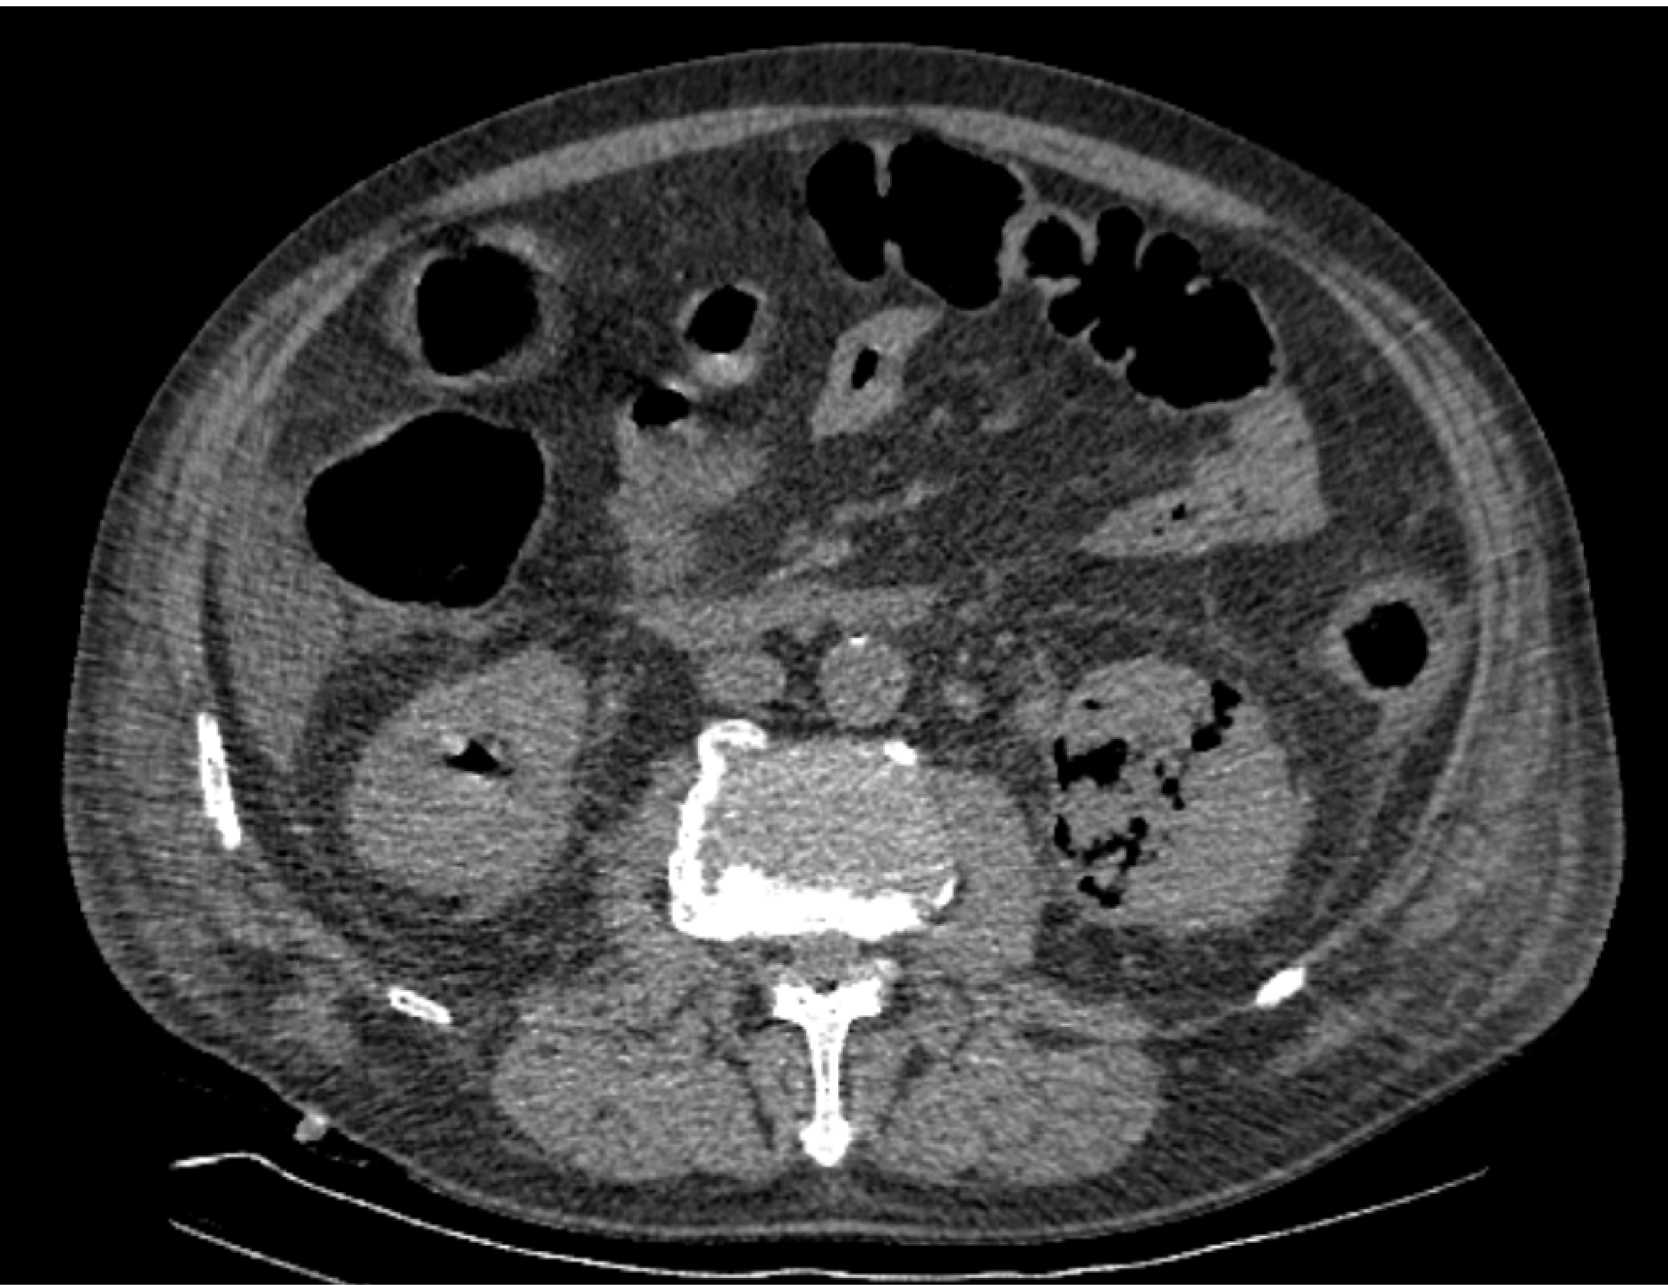

На следующий день состояние пациента оставалось тяжелым, с отрицательной динамикой, креатинин сыворотки возрос до 735,2 ммоль/л, Появились жалобы на слабость, тошноту. При осмотре: живот мягкий, вздут по всем отделам, при пальпации болезненный. Область почек не изменена, при пальпации безболезненна, патологических изменений в области почек не выявлено. Симптом поколачивания отрицательный билатерально. При УЗИ были обнаружены плевральный выпот по 300–400 мл с каждой стороны, гепатомегалия, увеличение размеров селезенки, асцит. Кроме того, в обеих почках были визуализированы тени, характерные для конкрементов. По данным компьютерной томографии (КТ) конкрементов не обнаружено, но в лоханке, на всем протяжении левого мочеточника и, частично, в правом мочеточнике, а также в мочевом пузыре визуализировался газ (рис. 1–6).

Рис. 3. Компьютерная томография органов брюшной полости, забрюшинного пространства, органов малого таза. Газ в левом мочеточнике

Рис. 4. Компьютерная томография органов брюшной полости, забрюшинного пространства, органов малого таза. Газ в почках

Рис. 5. Компьютерная томография органов брюшной полости, забрюшинного пространства, органов малого таза. Газ в левой почке